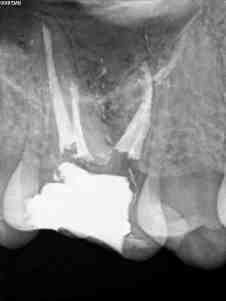

C) Por último, no encontramos un 1.6 con otra pulpitis irreversible.

C)

Todos los casos los tratamos igual, con ayuda del microscopio, localizamos los cuatro conductos, instrumentamos con sistema Mtwo, y obturamos con sistema de condensación vertical con ola contínua para hacer el downpack y pistola Obtura II para hacer el backfilling.

Lo que tienen estos tres casos en común, y por lo que decido colocarlos, es por la importancia que tiene la irrigación, por que hay veces que aunque en molares superiores localicemos el conducto Mesio-palatino,  puede que su salida se bifurque y nuestra lima no pueda seguir el conducto por que tiende a seguir recto uniendose al MV.